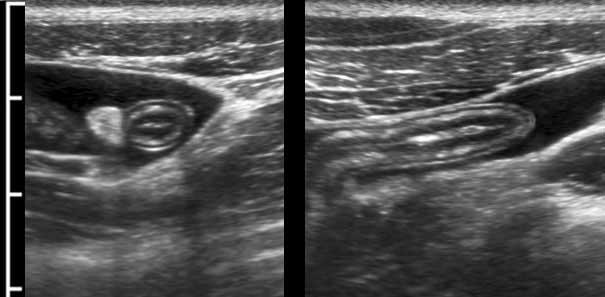

Intussusception

Đây là hình ảnh siêu âm của một trẻ 2 tuổi bị lồng ruột hồi manh tràng từng đợt, được khám trong khoảng thời gian giữa các cơn.

Hồi tràng với nhiều mảng Peyer sa vào manh tràng.

Hình ảnh siêu âm kinh điển của lồng ruột hồi-manh tràng ở hai trẻ khác nhau.

Trong cả hai trường hợp, đoạn hồi tràng bị lồng được định vị không đối xứng bên trong ống lồng ngoài, do mạc treo ruột tăng âm có chứa mỡ, bám vào hồi tràng và đi theo hồi tràng khi bị kéo vào trong.

Trong mạc treo, siêu âm cho thấy một hạch bạch huyết mạc treo (hbh) phóng đại ở cả hai.

Các hạch này phì đại như một phần của tình trạng tăng sản hạch bạch huyết toàn thân và khônghu trú trong lòng hồi tràng.

Do đó đây không phải là điểm dẫn đầu nguyên phát. Ở bệnh nhân bên phải, ruột thừa (mũi tên) cũng bị kéo vào trong.

Lưu ý cấu trúc đa lớp của thành bụng phía trước của phức hợp lồng ruột, đại diện cho ba lớp thành ruột bị gấp lại.